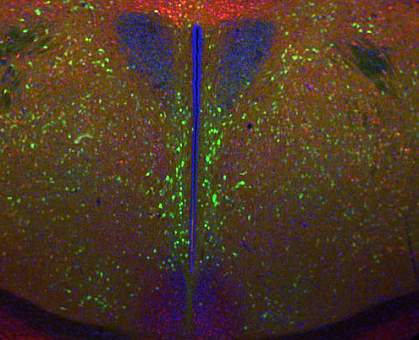

You naturally lose brain cells with age. Certain regions of the brain have cells called neural stem cells that can regenerate. These stem cells serve as a sort of internal repair system, dividing to replenish other cells. They have only been found in a few brain regions, including the hypothalamus. The hypothalamus is critical for regulating the endocrine system—the glands and hormones throughout the body. The region is known to play a role in development, reproduction, and metabolism. It has also recently been implicated in aging.

The researchers first observed what happens to stem cells in the hypothalamus as healthy mice age. They found that the number of stem cells gradually diminished in early to middle-aged mice and were almost completely absent in older mice. They then experimentally disrupted these stem cells in middle-aged mice and examined the effects on aging over 3–4 months. Mice with the disrupted stem cells showed signs of cognitive impairment and other signs of aging earlier than control mice. Mice with the disrupted stem cells also had a shortened lifespan.

The researchers were able to slow these signs of aging by implanting hypothalamic stem cells harvested from newborn mice into the brains of middle-aged mice. The mice also lived longer than control mice. These anti-aging effects could be replicated by injecting the tiny fluid-filled sacs, called exosomes, that are secreted by hypothalamic neural stem cells. Exosomes circulate in blood and carry genetic material called miRNA, which regulates genes in tissues throughout the body.